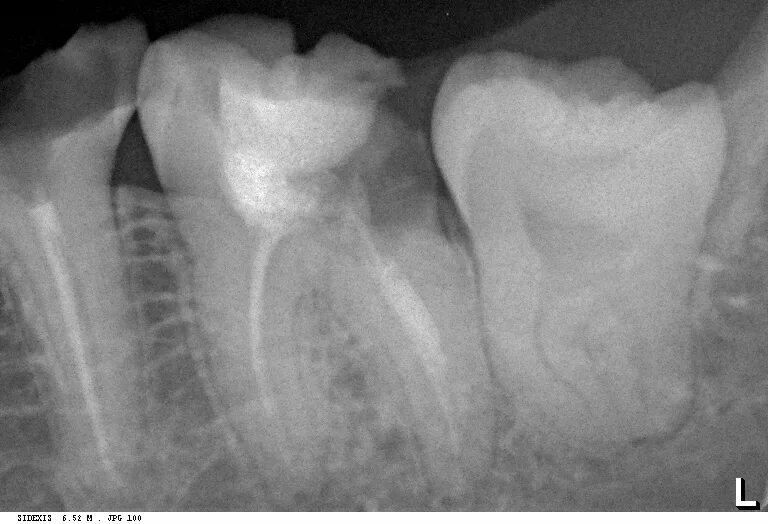

Удалить зубы семерки